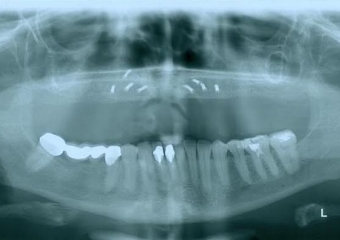

Raio - x Panorâmico Implantes

Raio-x Panorâmico com prótese provisória